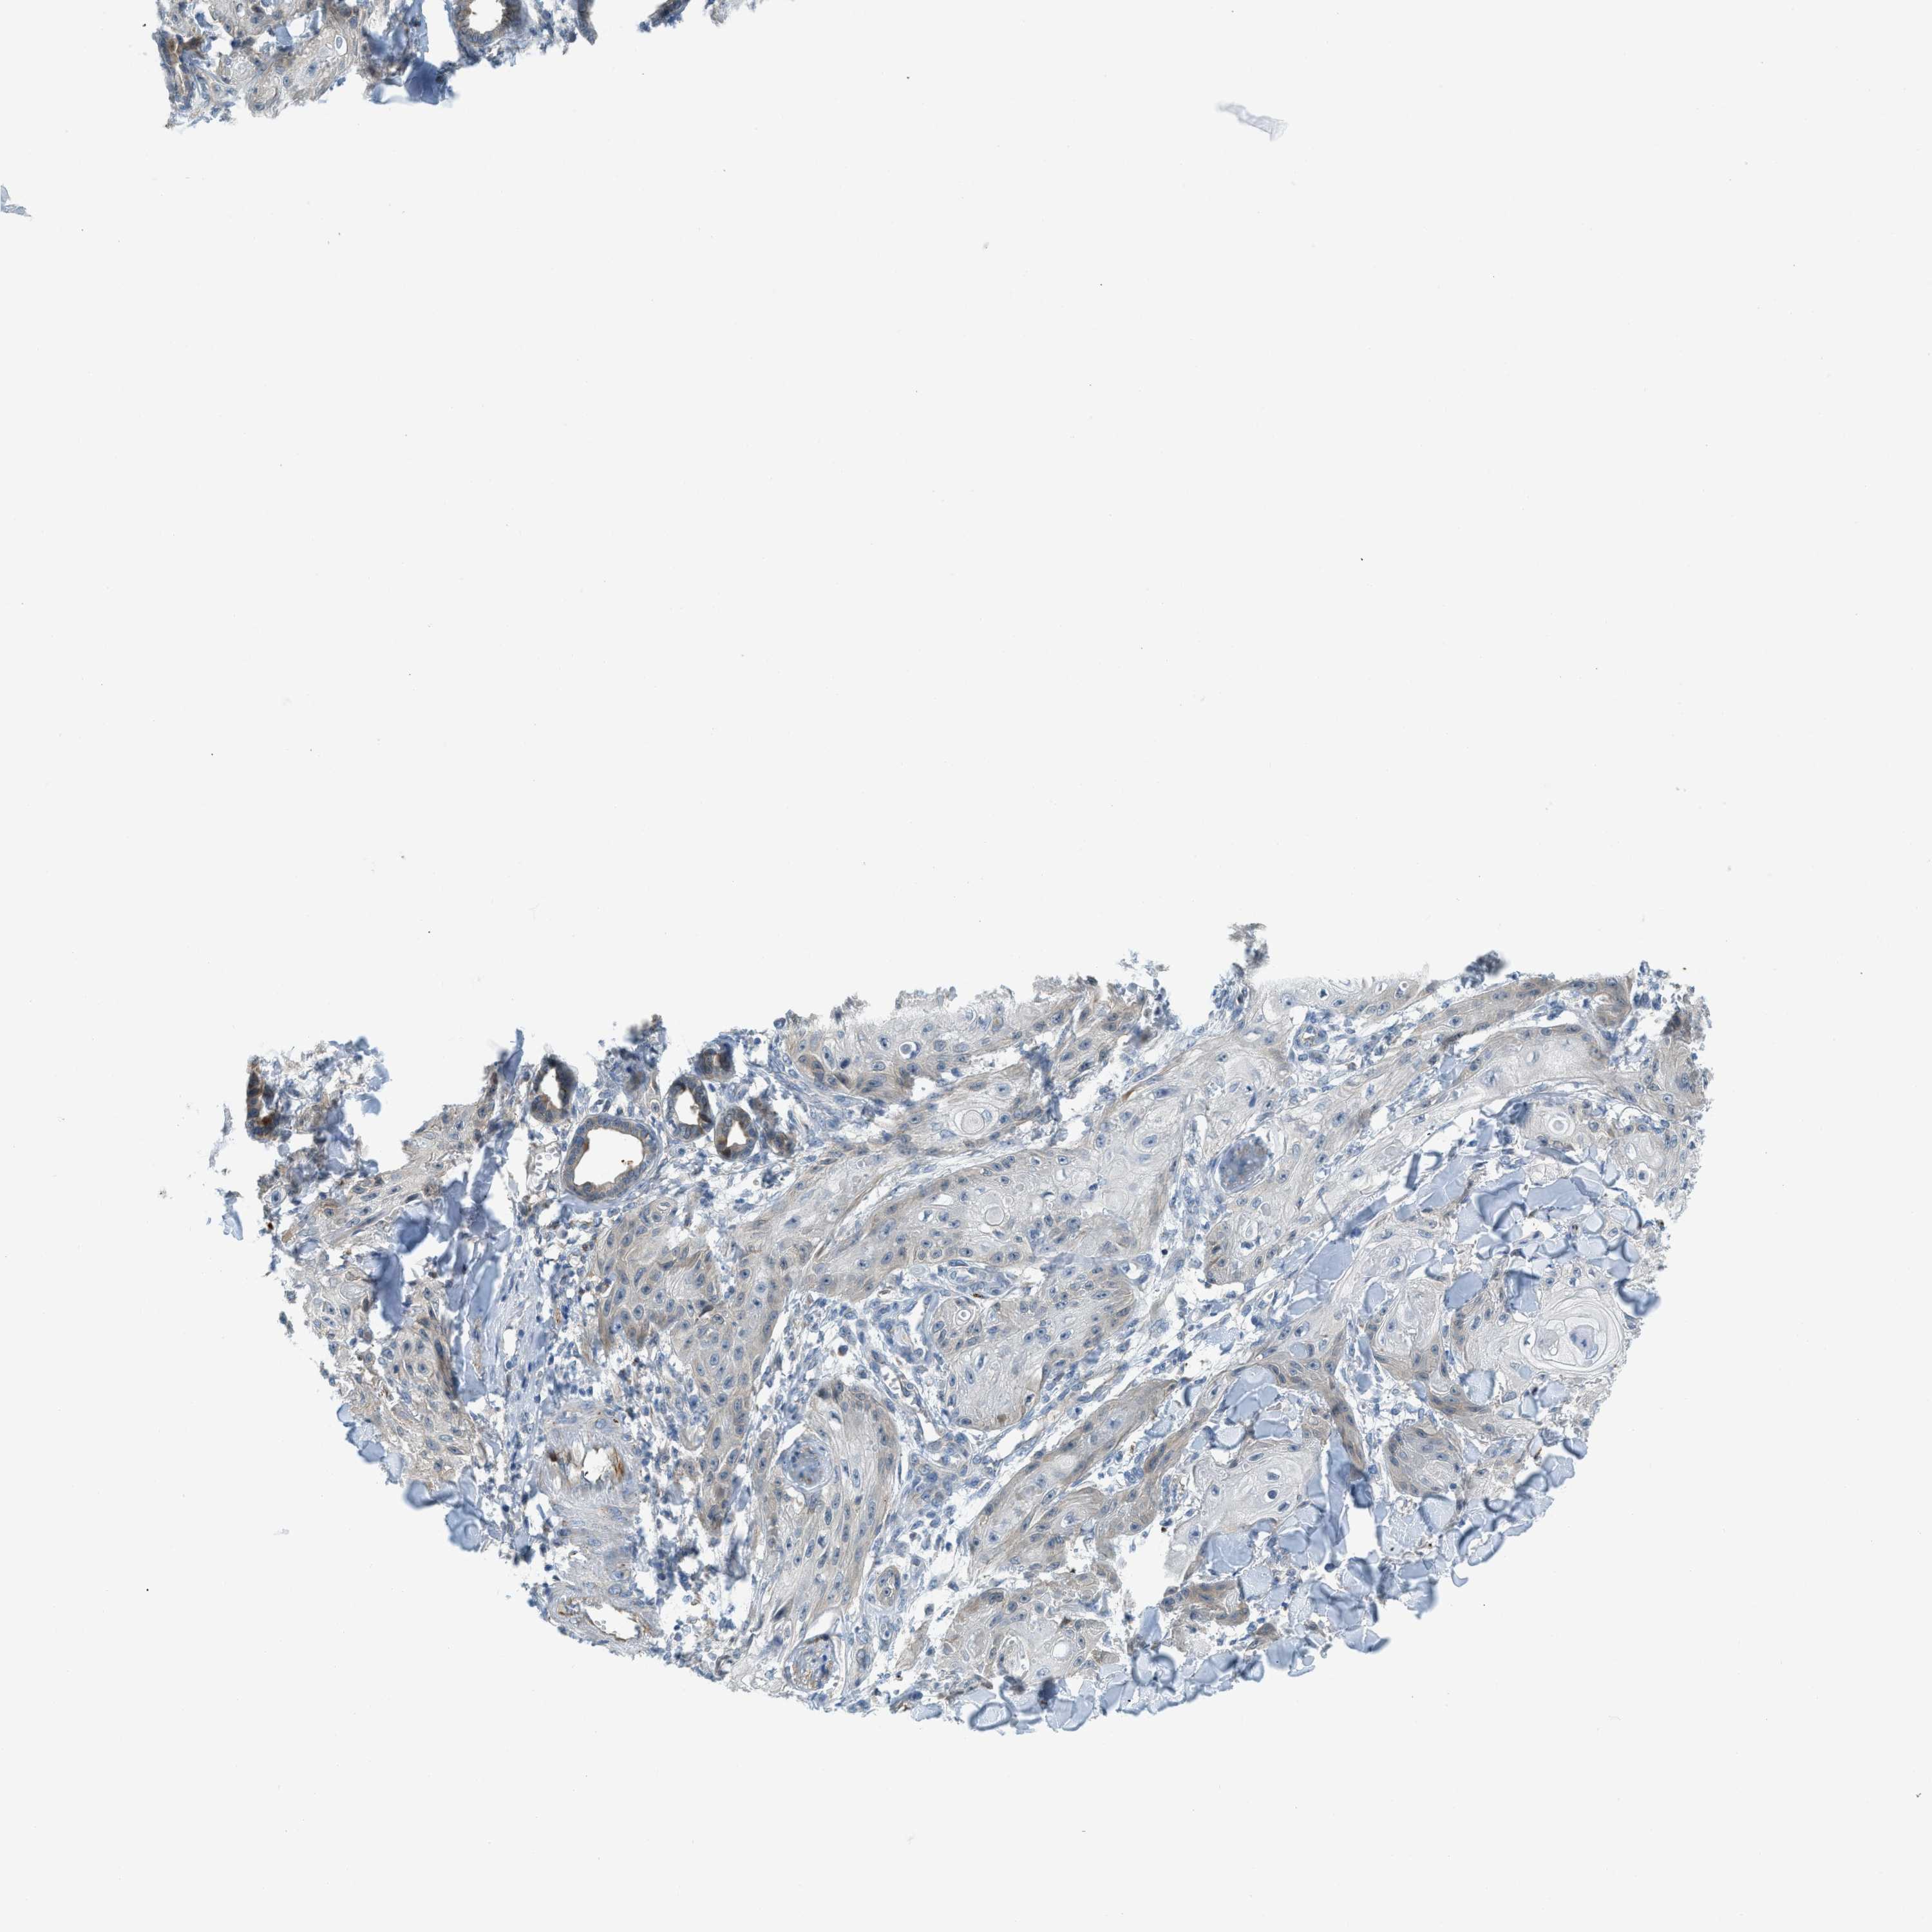

Basal cell and squamous cell cancer

SKIN CANCER - Protein expressioni

A mouse-over function shows sample information and annotation data. Click on an image to view it in a full screen mode. Samples can be filtered based on level of antibody staining by selecting one or several of the following categories: high, medium, low and not detected. The assay and annotation is described here.

Each image is clickable and will lead to virtual microscopy that enables deeper exploration of all samples and also displays staining intensity scores, fraction scores and subcellular localization as well as patient and tissue information for each sample.

Antibody CAB016416

Squamous cell carcinoma, metastatic, NOS

Squamous cell carcinoma, NOS